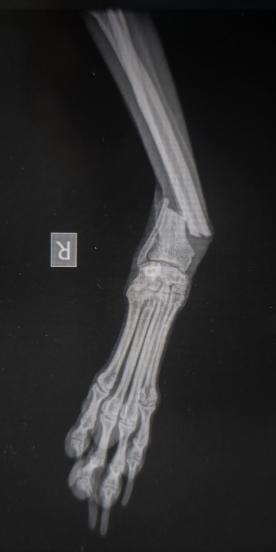

Geschlossene Unterarmfraktur